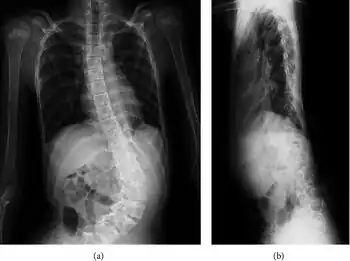

People with Shprintzen-Goldberg syndrome can experience a range of symptoms that vary in severity. Due to craniosynostosis, people with SGS may have a long and narrow head, wide spaced protruding eyes that may slant downwards, a high and narrow palate, a high and prominent forehead, a small lower jaw, and low-set posteriorly-rotated ears. Some other skeletal abnormalities people with SGS may experience include joint hypermobility, clubfoot, scoliosis, camptodactyly, arachnodactyly, long limbs, and a chest which appears to sink in or stick out. Other symptoms that may be experienced include brain abnormalities (i.e. hydrocephalus), developmental delays, intellectual disability, gastrointestinal problems (i.e. constipation, gastroparesis), abdominal or umbilical hernias, easily bruised skin, trouble breathing, and hypotonia. Some cardiac issues which are occasionally seen in people with SGS include aortic aneurysm, aortic regurgitation, aortic root dilation, mitral valve regurgitation, and mitral valve prolapse.[4]

a) X-ray—anterior-posterior view of levoscoliosis b) X-ray—lateral view.